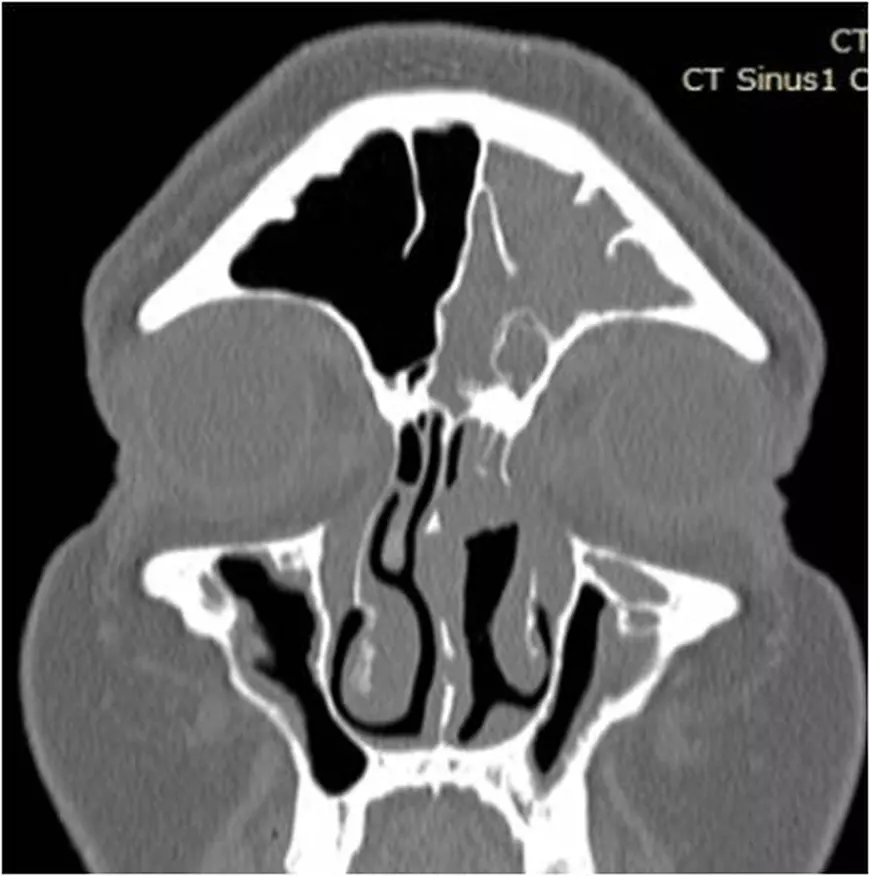

Mihai S. avea obstrucție nazală pe partea stângă, secreții muco-purulente abundente și dureri de cap acerbe. Ȋn urma primei intervenții chirurgicale, s-a îmbunătățit obstrucția nazală, cantitatea de secreții a scăzut, în schimb, durerea și presiunea de la nivelul sinusului frontal au rămas constante. La CT-ul de control, de după operație, s-a observat că cele două sinusuri operate anterior, maxilar și etmoidal, fuseseră curățate. În schimb, sinusul frontal apărea plin cu puroi, ceea ce ȋnsemna că este necesară o nouă intervenție, pentru abordul acestui sinus. Echipa medicală de la Spitalul Memorial Băneasa, sudată ȋn sute de operații, ȋn ultimii șase ani, formată din conf. dr. Vlad Budu, medic primar ORL și dr. Silviu Crăc, medic specialist ORL, a decis să folosească o metodă chirurgicală minim invazivă.

Pentru Mihai S. am folosit tije endoscopice angulate și instrumentar angulat adecvat chirurgiei endoscopice frontale. Am reușit să ajungem în sinusul frontal, să ȋl golim de secrețiile purulente și să lăsăm un orificiu deschis, pentru a ȋmpiedica o recidivă și a asigura drenajul și ventilația, ceea ce înseamnă funcționalitate normală”, completează dr. Budu.